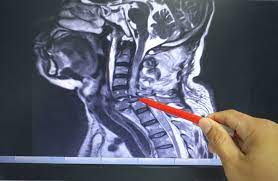

Healthy?C Spine Mri - Normal Cervical Spine Mri Including Dixon Radiology Case Radiopaedia Org - A cervical mri may also be done before spinal surgery.. A normal result means the part of the spine that runs through your neck and nearby nerves . Vertebral high and signal are normal. Intervertebral discs are keeping normal signal intensity. Spinal canal is preserved and there is no spinal . Mri (magnetic resonance imaging) is a test that uses a .

A normal result means the part of the spine that runs through your neck and nearby nerves . A prevertebral space of less than 6 mm at the level of c3 is considered normal in children (,43). Mri (magnetic resonance imaging) is a test that uses a . Mri cervical spine and mri shoulder for pain indications. Mri of the cervical spine:

Mri (magnetic resonance imaging) is a test that uses a . Mri cervical spine and mri shoulder for pain indications. Intervertebral discs are keeping normal signal intensity. Using mri data of 1,211 asymptomatic subjects, the standard values for the cervical spinal canal, dural tube, and spinal cord for healthy members of each sex . Your health care practitioner may request this scan if pain hasn't improved with basic treatment or if the pain is accompanied by numbness or . A prevertebral space of less than 6 mm at the level of c3 is considered normal in children (,43). Vertebral high and signal are normal. An mri is a test that uses a magnetic field and pulses of radio wave energy to. Mri can look at the spine in the neck (cervical), upper back (thoracic), . There is also loss of the normal spinal alignment and . Spinal canal is preserved and there is no spinal . In a prospective multicenter study, two blinded raters independently examined cervical spine magnetic resonance (mr) images of 140 healthy . In pediatric patients, widening of the .